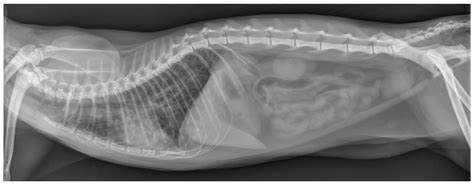

• Radiographs (X-rays): Chest X-rays can reveal inflammation, fluid, or other abnormalities in the lungs.